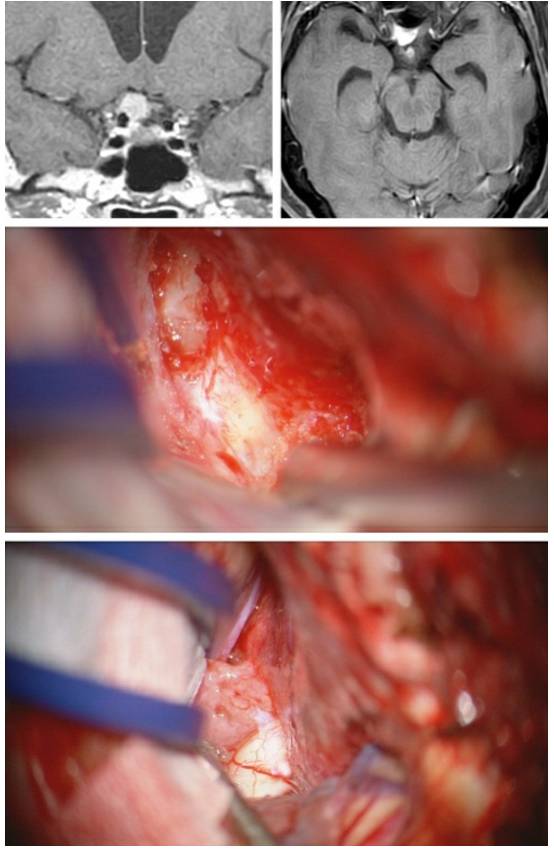

图2. 根据蝶骨嵴内侧型脑膜瘤是否侵犯内侧神经血管和包绕颈动脉穿支血管,可表现出不同的手术难度。上图所示为一例向内侧轻度延伸的脑膜瘤,侧裂大脑中动脉分支覆盖在肿瘤的上极。下图所示为一例真正意义上的蝶骨嵴/床突内侧型脑膜瘤,向内侧显著生长并包绕ICA。

图3. 一例第三组或右侧视神经孔脑膜瘤。肿块所处的关键位置导致相对快速的视力恶化,使得肿瘤在早期得以发现。

图4. 冠状位和轴位图片显示蝶骨嵴中部/内侧脑膜瘤与周围血管结构之间的典型关系。往往可发现更为明显的视器受压的证据。